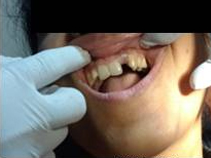

Pre Operation

Single Tooth Implant

Placement of Bone Grafting

Use of Bone Graft & GTR membrane for an Implant